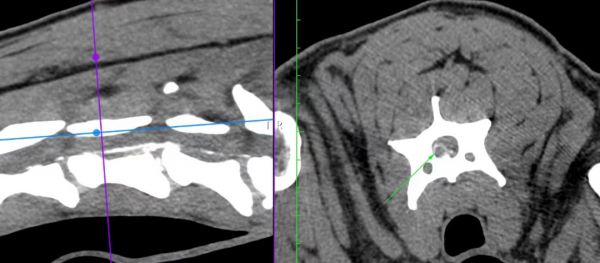

CT检测结果显示C4-C5汉森I型椎间盘脱出压迫神经